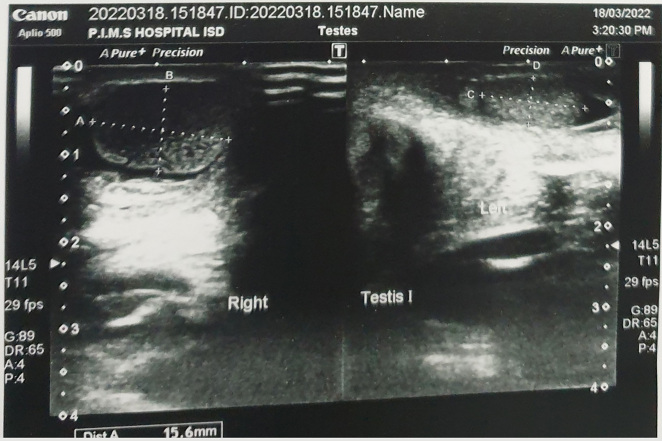

Case presentation: We present here the case of a two-day old neonate with in-born right scrotal swelling admitted at Children's hospital. The patient was born at term via cesarean section at a private hospital. Upon arrival in the emergency department, he was well hydrated, pink at room temperature with good perfusion. Upon examination, the right testis was found to be enlarged, tense, non-tender visibly reddish with overlying skin excoriation. Trans-illumination was negative in right but positive in the contralateral testis. Both hernial orifices were normal. Doppler ultrasound of the inguinoscrotal area found the right testis to be enlarged (15.6*9.4 mm) and showed heterogeneous hypoechoic texture with prominent rete testis and no flow on color doppler analysis. An urgent scrotal exploration was undertaken. Intra-operatively there was frank necrotic right testis with intravaginal torsion of the testis and minimal hydrocele. A right orchidectomy and contralateral orchidopexy were performed.